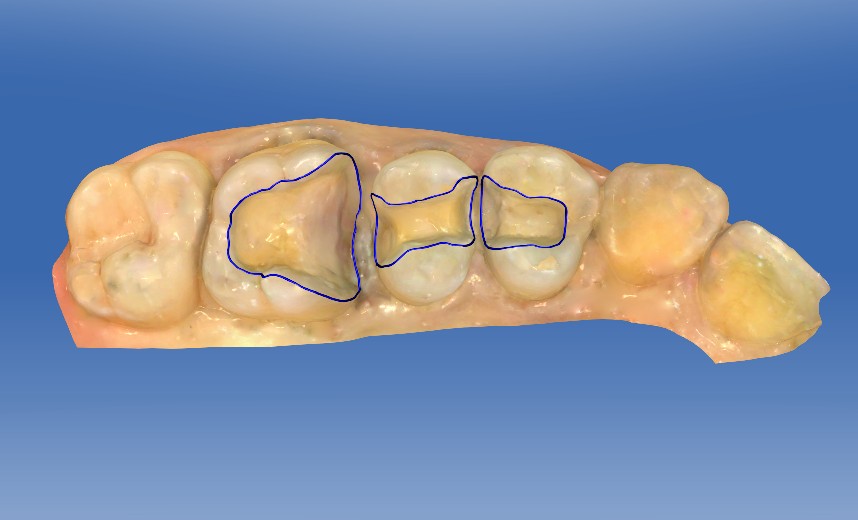

0.1%的聚维酮碘溶液局部消毒,涂表麻膏,4%盐酸阿替卡因肾上腺素注射液0.8ml局部浸润麻醉,等待麻药生效后。去净腐质,基牙预备基牙预备,排龈,精修,CEREC扫描,比色,CEREC制作嵌体,试戴后边缘密合,符合各种对修复体的质量和设计要求,患者满意,同意粘固。消毒基牙和修复体,酸蚀冲洗,隔湿,吹干,粘接做永久固定,调合抛光,交代注意事项,常规医嘱,按时复诊,客户表示一次就诊方便快捷,很满意。